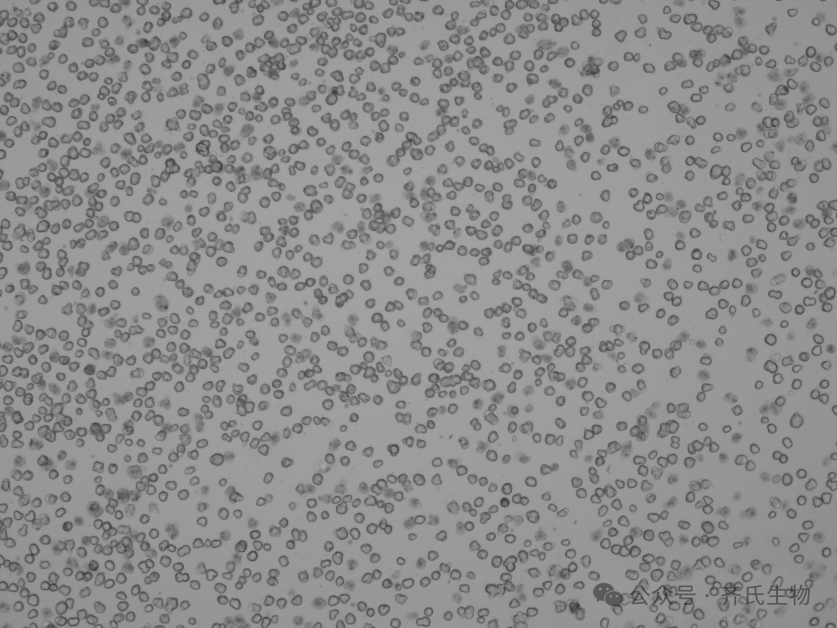

☆ 悬浮肝实质细胞

悬浮肝细胞一般用于代谢稳定性研究或代谢物谱研究,在最开始的4-6h内效果最佳。